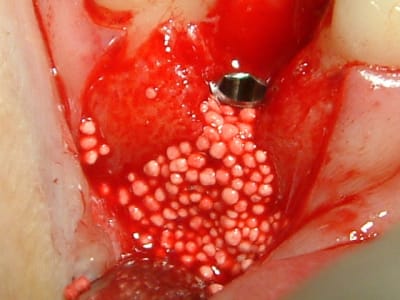

ce matin, j'ai essayé le cerasorb avec une membrane Tefgen... qui a une expérience de ces matériaux?

voici les clichés et j'ai hâte de voir ce que çà va donner..

@+

(oups, ouvrir dans l'ordre cliché 31, 32 etc...)

j'aime beaucoup ce que tu fais mais sur ce coup là tu vas être déçu... mon expérience de ce bio métaériau c'est que ça reste dans l'tétat qu'il était au moment de l'insertion et l'os ... bof, je suis sûr que ça marche mieux sans